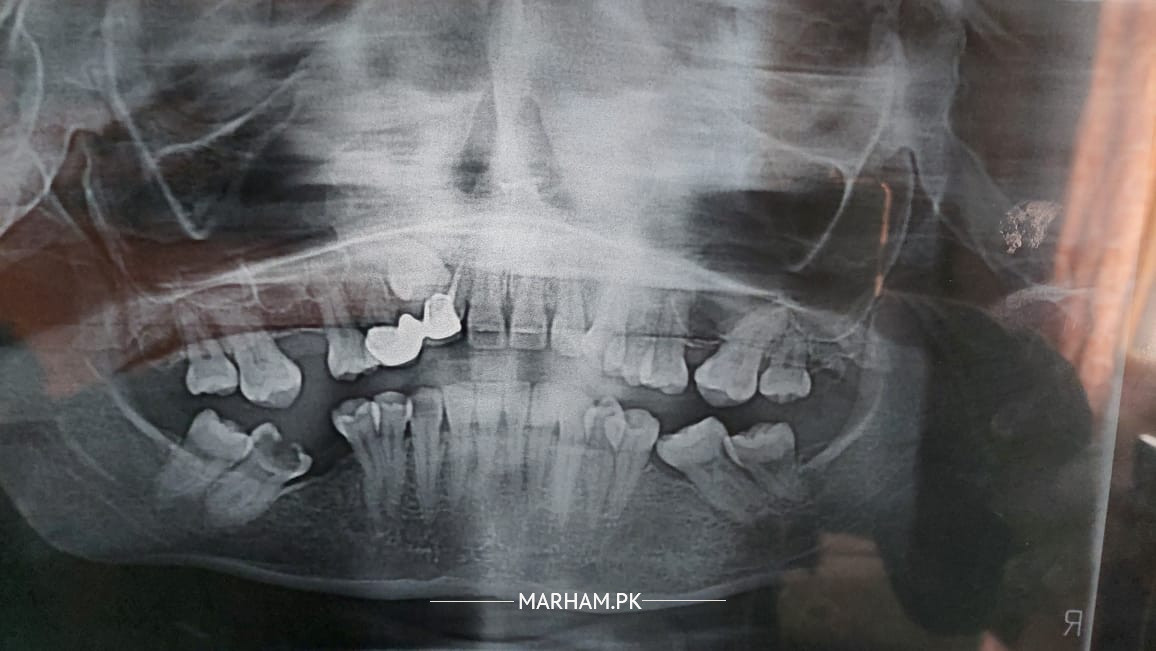

The question is related to impacted canain teeth. July me braces lagwe the then mid December surgery hoi impacted canain teeth kely surgery ko one and half month hogae dant appear nahi hoa. doctor ka kehnna ha ke agar dant bahr nahi ata to hum dubara surgery ye pochna ha ke kya ye normal ha aik hi dant kelyen dou dafa surgery karna ?mujhe dubara surgery nahi karwana to kya koi behtr option ha stuck teeth kelye.

Please check xrays

Xrays